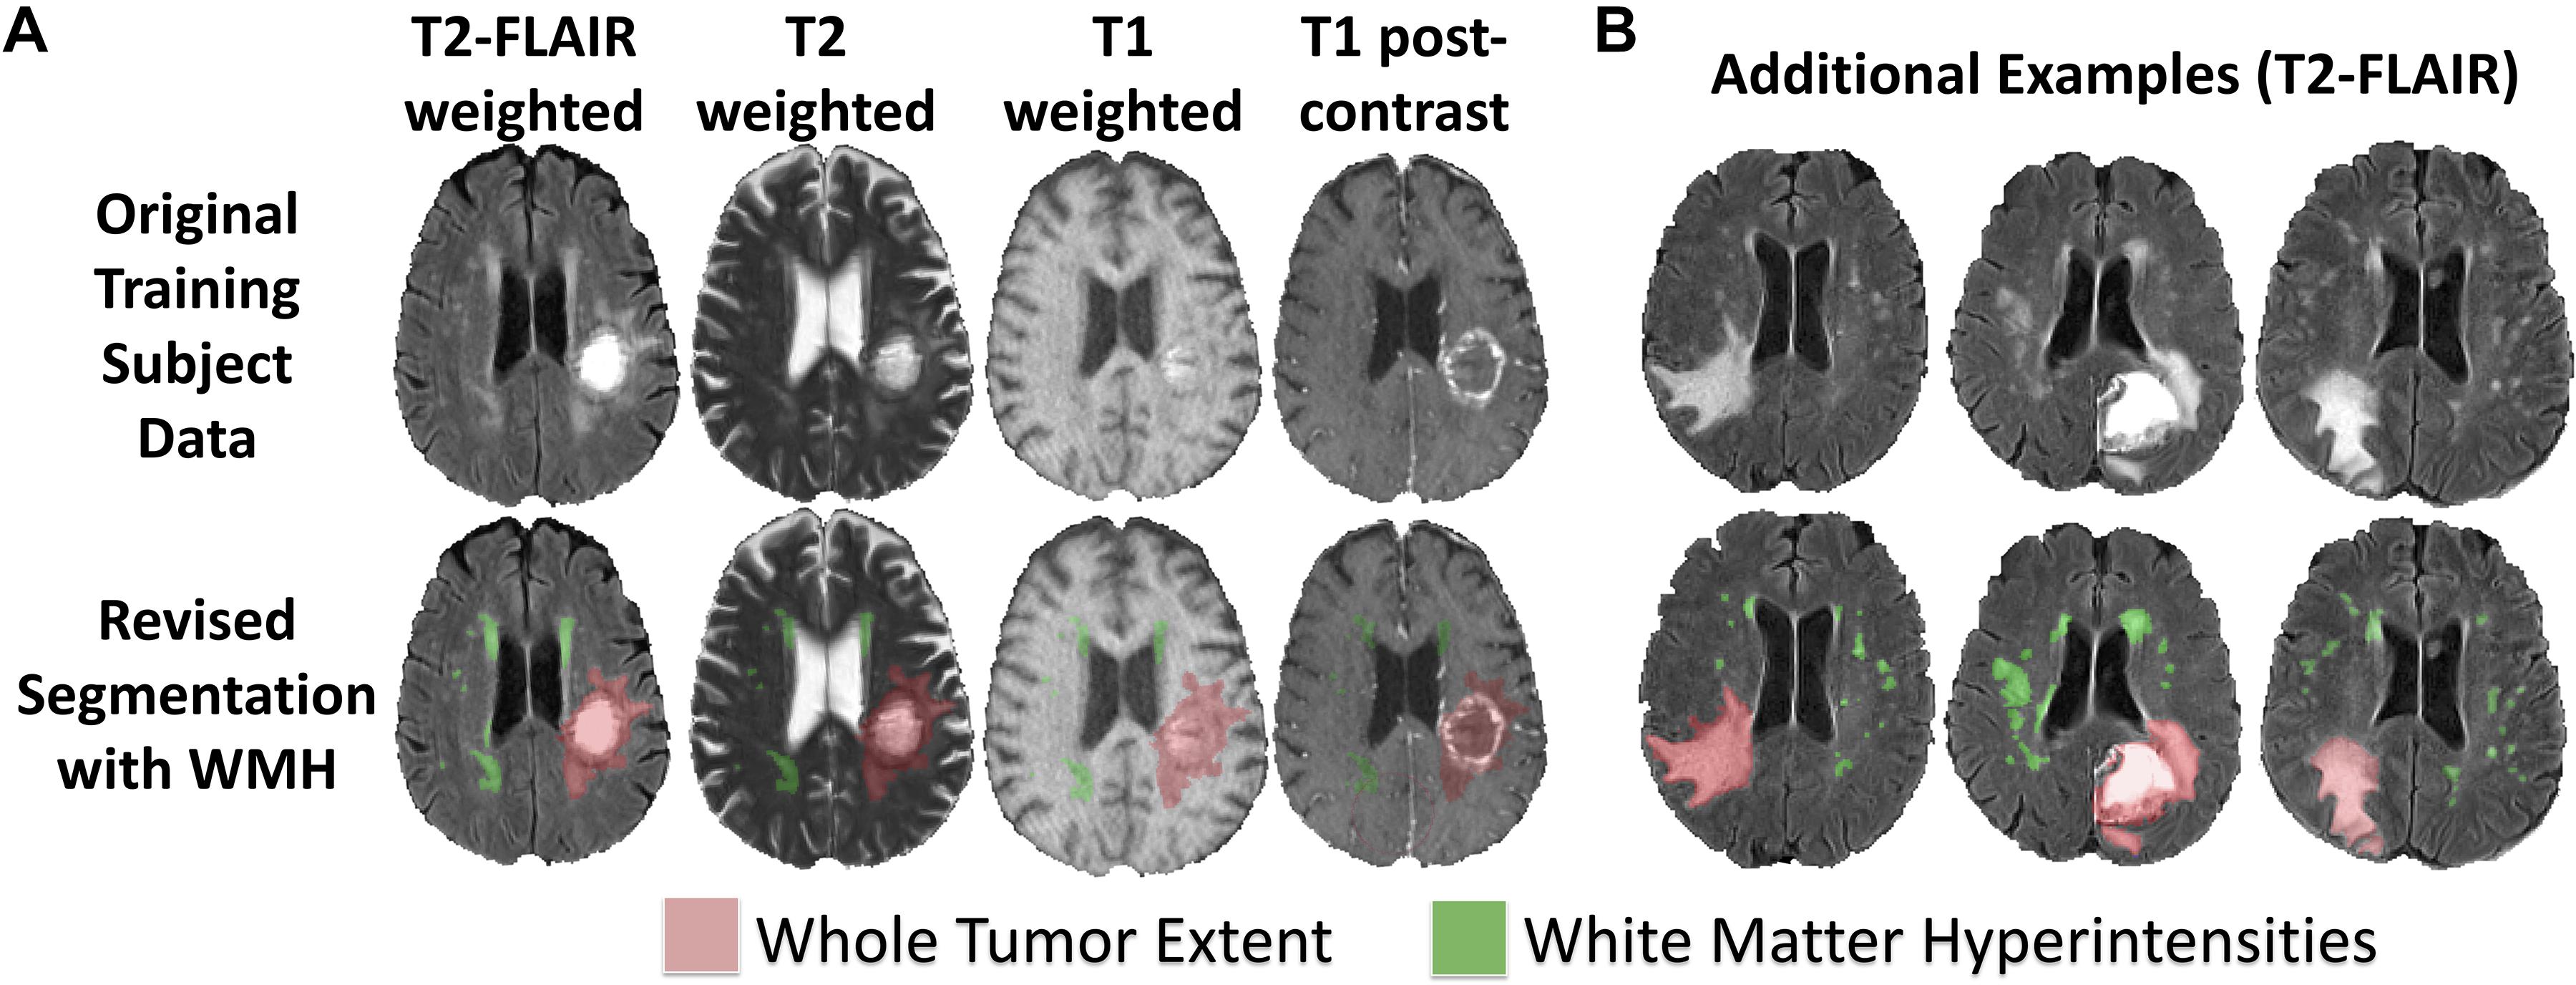

Fazekas grades. T1 t2 Flair. MRI t1 t2. T1 t2 мрт. T1 t2 fleur мрт.

Fazekas grades. T1 t2 Flair. MRI t1 t2. T1 t2 мрт. T1 t2 fleur мрт.